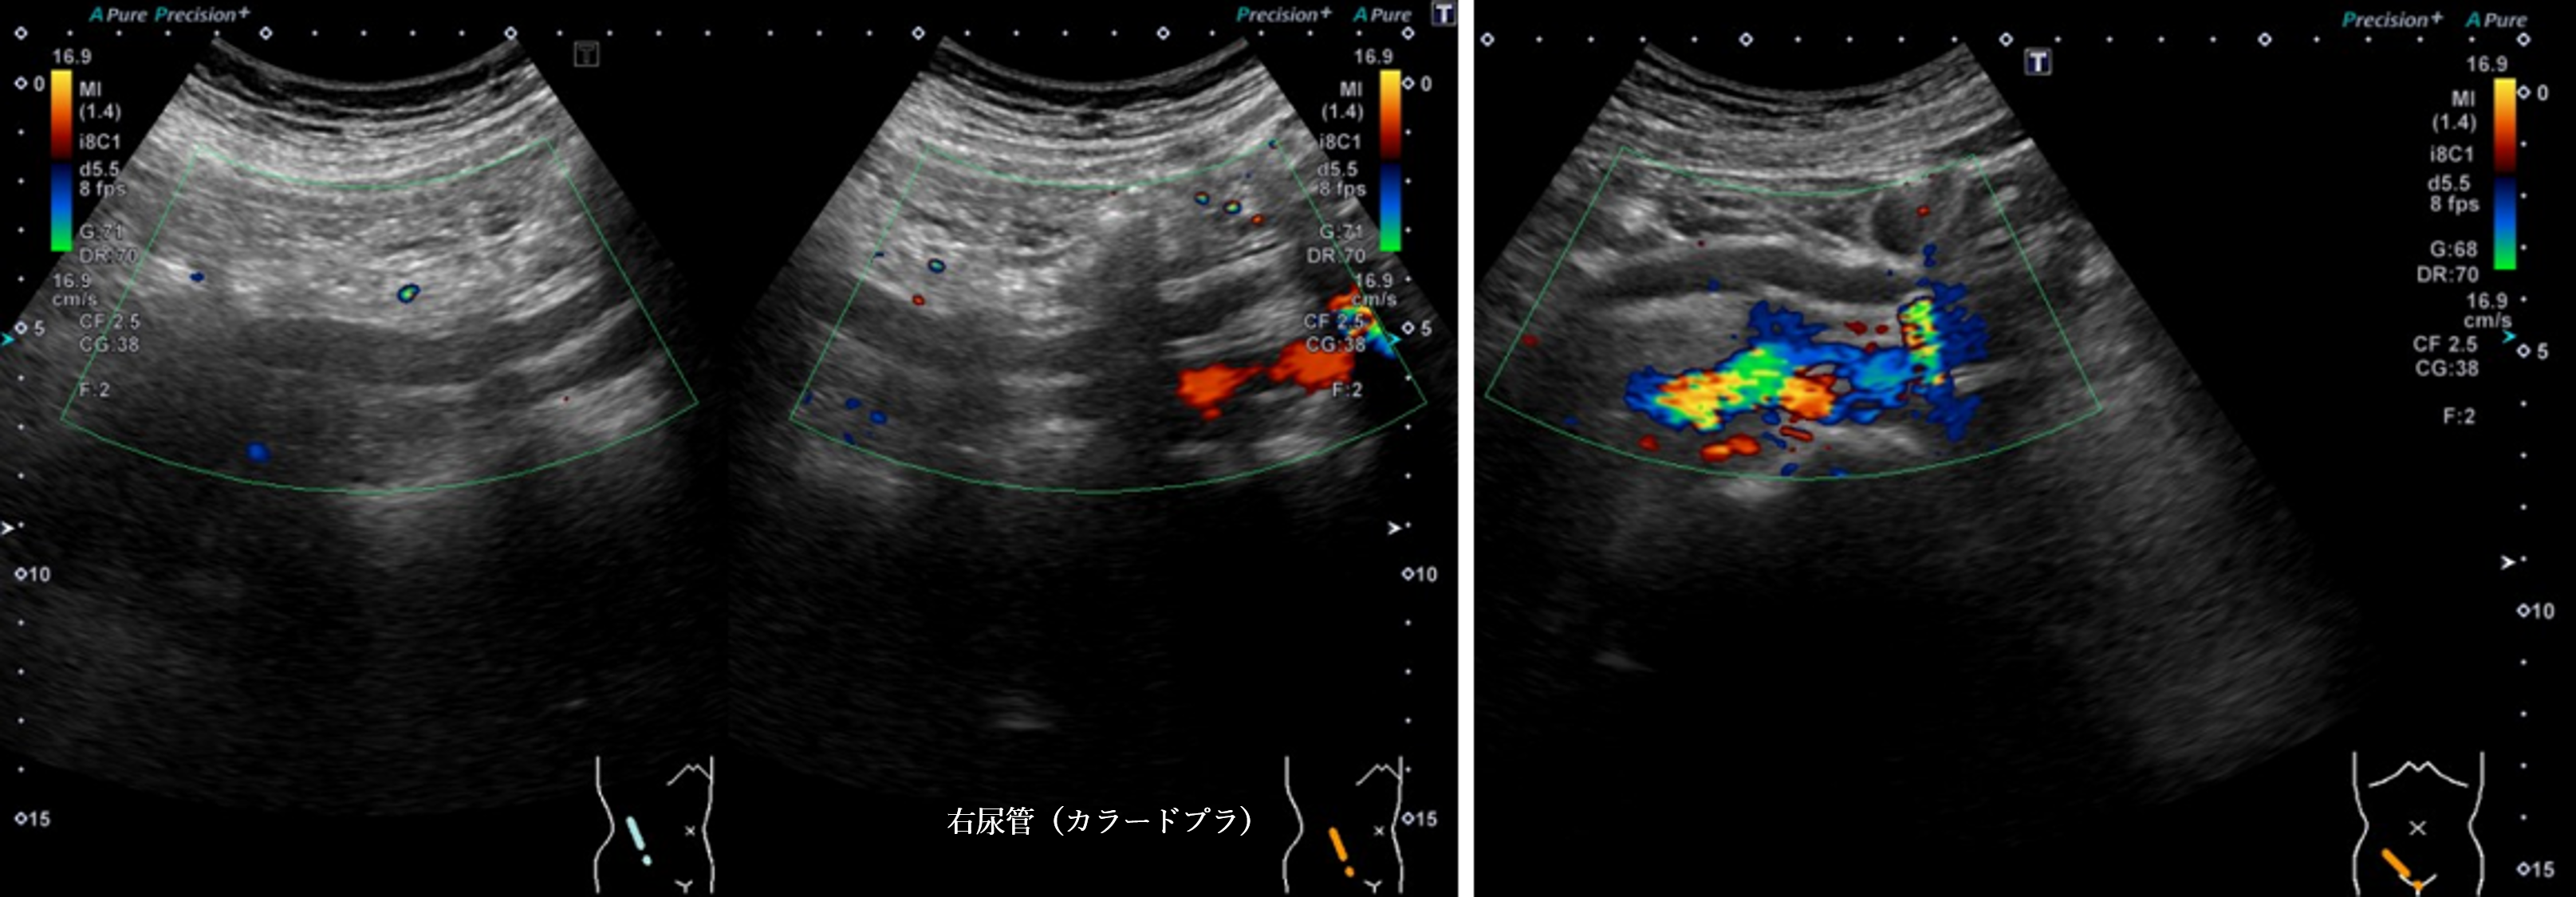

腹部超音波2 動画3 右尿管(No18-19_C)

腹部超音波2 動画3(No18.19_C)

① 右尿管内に充実性腫瘍像を認める

② 両腎内に strong echo 像を多数認める

③ 左腎に明らかな腎盂腎杯拡張は認めない

④ 右腎の腎盂拡張および右尿管拡張を認める

⑤ 右腎中心部エコー内に無エコー領域を認める